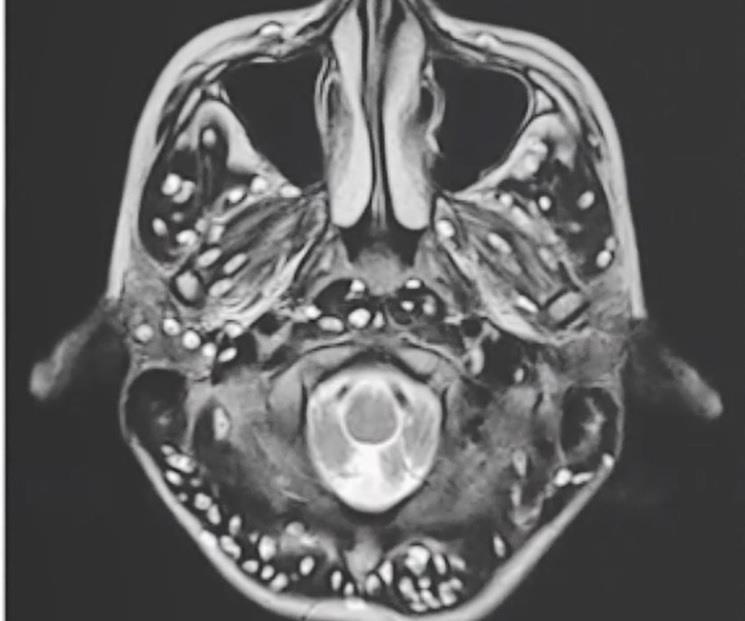

Các bác sĩ phát hiện trong não của thiếu niên có quá nhiều trứng sán làm tổ, gây ra tình trạng co giật. Bệnh nhân tử vong sau 2 tuần cấp cứu.

Sán lợn và các bệnh liên quan đến sán phổ biến ở những nước ở châu Á, châu Phi và châu Mỹ La Tinh. Nguyên nhân chính tới từ thói quen ăn uống những loại thực phẩm chưa nấu chín.